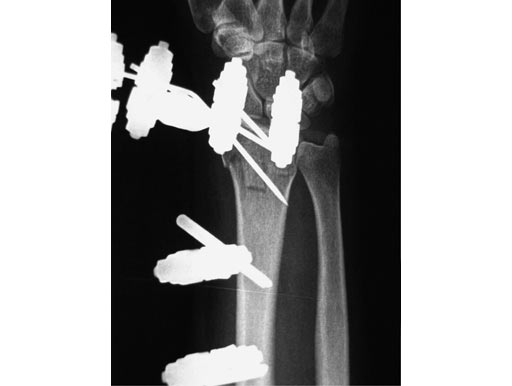

Treatment of fractures of the distal radius has been proven to be advantageous if spanning of the wrist joint is avoided. This allows for greater motion throughout the treatment resulting in improved range of motion, grip strength, and dexterity. The nonspanning Distal Radius Fixator provides such a nonbridging external fixator, creating a low-profile frame for increased patient comfort and the ability to perform daily activities.

The nonspanning Distal Radius Fixator consists of a small adjustable clamp, nonspanning, MR safe. It locks on to two 4.0 mm Schanz Screws spaced 20 mm apart. The 4.0 mm carbon fiber rod slides into a through hole in the clamp with a set screw tightening point to established the desired length. A ball joint in the clamp then provides for ulnar/radial as well as volar/dorsal deviation of the rod. To create lower profile frames, the nonspanning Distal Radius Fixator includes three shorter length Schanz screws65 mm lengths in both 4.0/2.5 mm size (with a trocar tip) and the 4.0/3.0 mm size (with a self-drilling tip), and an 80 mm length in the 4.0/2.5 mm size (with a trocar tip).

The 4.0 mm curved carbon fiber rods match the axial curvature of the wrist. They are available in 60, 90, 120, or 180 arcs to be used for fixation of the distal fragment.

The 4.0 mm angled T-bar carbon fiber rods create the same angle as the curved rods, with the addition of a rod extending perpendicularly. The material allows a frame to be constructed with a rod centred on the dorsal aspect of the wrist without sacrificing the C-arm image in the dorsal/palmar view. The angled T-bar fiber rods will be available in 80 mm (length) 50 mm (width), 80 120 mm, 110 50 mm, and 110 120 mm. Both the curved and angled T-bar fiber rods can be used as part of a delta frame construct.

56-year-old female, accident at home